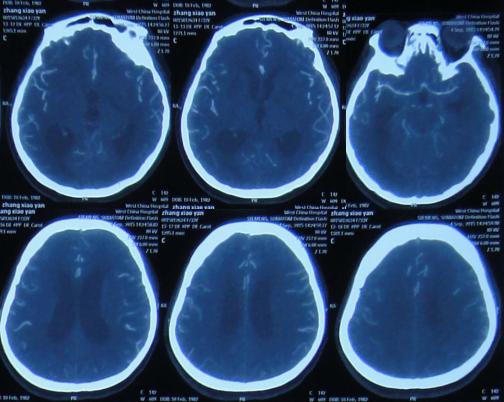

第1家医院治疗13天后即2015年8月16日,查头CT:双侧侧脑室,三脑室及四脑室扩张(图-4),且给予腰穿检查,提示颅压高(脑脊液检查结果不详),给予相关对症治疗。

图-4:2015年8月16日头部CT